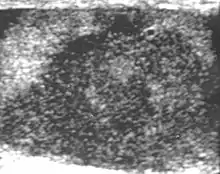

Embryonal cell carcinomas, a more aggressive tumor than seminoma usually occurs in men in their 30s. Although it is the second most common testicular tumor after seminoma, pure embryonal cell carcinoma is rare and constitutes only about 3 percent of the nonseminomatous germ cell tumors. Most of the cases occur in combination with other cell types. At ultrasound, embryonal cell carcinomas are predominantly hypoechoic lesions with ill-defined margins and an inhomogeneous echotexture. Echogenic foci due to hemorrhage, calcification, or fibrosis are commonly seen. Twenty percent of embryonal cell carcinomas have cystic components. The tumor may invade into the tunica albuginea resulting in contour distortion of the testis [Fig. 4].